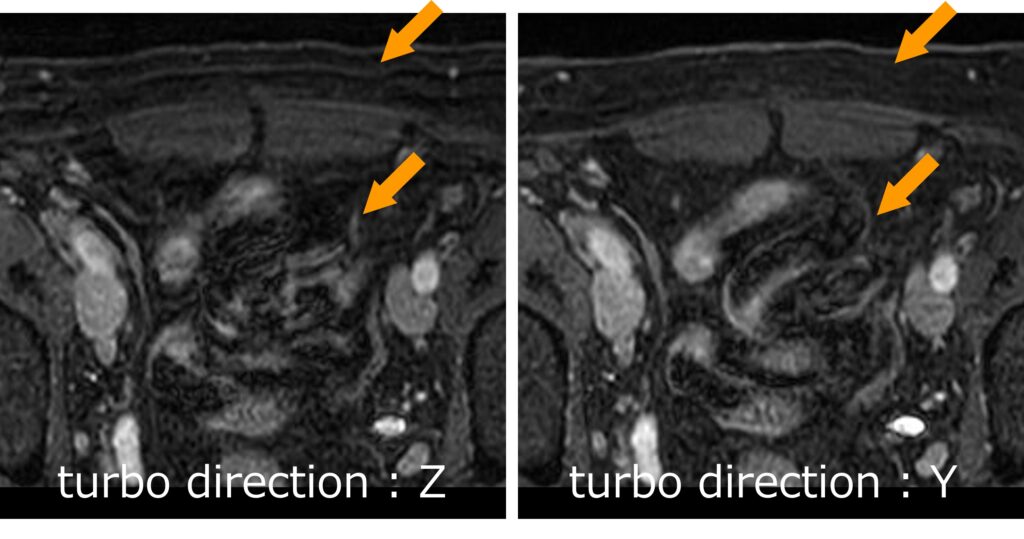

3D高速グラディエントエコー法は3D撮像になりますので、位相方向のみならず、スライス方向にも位相エンコードが行われます(Fig.2)。したがって、3D高速グラディエントエコー法では2方向のk-space充填方向を考える必要があります。Philipsの3D-TFEでは、ContrastタブにおけるTFE turbo directionで先に充填するk-spaceの方向を決定します(Fig.3)。例えば、turbo direction = Z の場合、スライス方向を優先的にdata samplingすることになります。つまり、Z(スライス)方向のk-spaceが1列充填されると、Y(位相)方向のk-spaceを1列移動し、また、Z(スライス)方向のk-spaceが1列充填されます(Fig.4)。そのため、先に充填するk-spaceの方向よりも、後からk-spaceを充填する方向のほうがk-space充填時間は長いことが分かります。したがって、モーションアーチファクトは後から充填する方向(Fig.4の場合、Y)に目立つことになります。

肝臓などの上腹部を横断面で撮像する場合、臓器の上下運動が大きいので、スライス方向のモーションアーチファクトを抑制するためにturbo directionをZ(スライス)方向に設定することが多いと思います。一方、骨盤部領域を横断面で撮像する場合、臓器の上下運動は小さいと予想されるため、腹壁からの動きなどを抑制するためにturbo directionをY(位相)方向に設定することで、スライス面内のモーションアーチファクトを抑制することができます。Fig.5に示すように、turbo directionをY(位相)方向に設定することで、腹壁や腸管の動きによるモーションアーチファクトを抑制することができ、腸管内が鮮明に描出されていることが分かると思います。